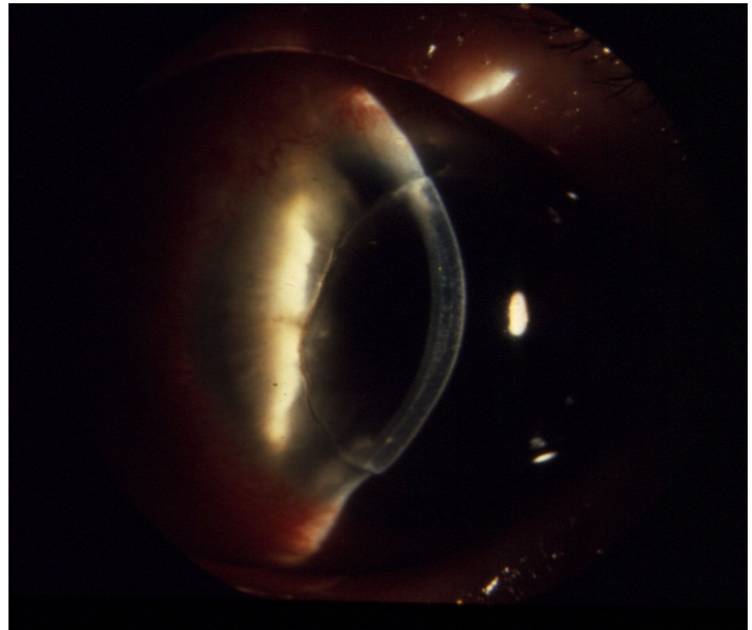

Рис. 8.2.11. Роговица и трансплантат прозрачны, незначительные складки десциметовой оболочки

Рис. 8.2.12. Трансплантат отдавливает задние слои роговицы в сторону передней камеры